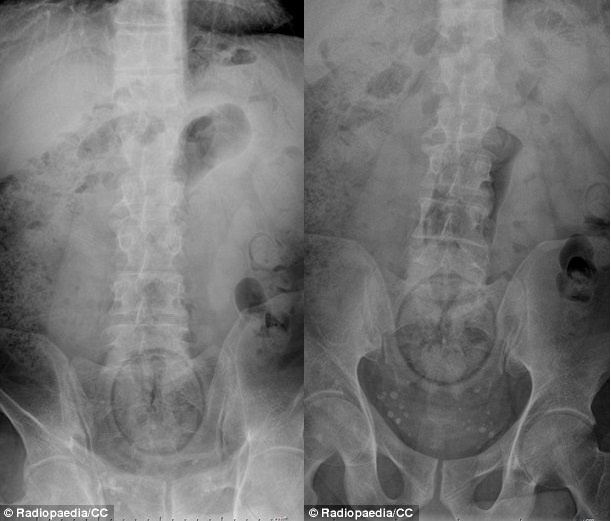

| Lọ cà phê nhỏ mắc kẹt trong cơ thể bệnh nhân. |

| Đồ chơi tình dục tự chế từ vỏ tuýp vitamin Berocca mắc kẹt trong trực tràng của một bệnh nhân nam. |